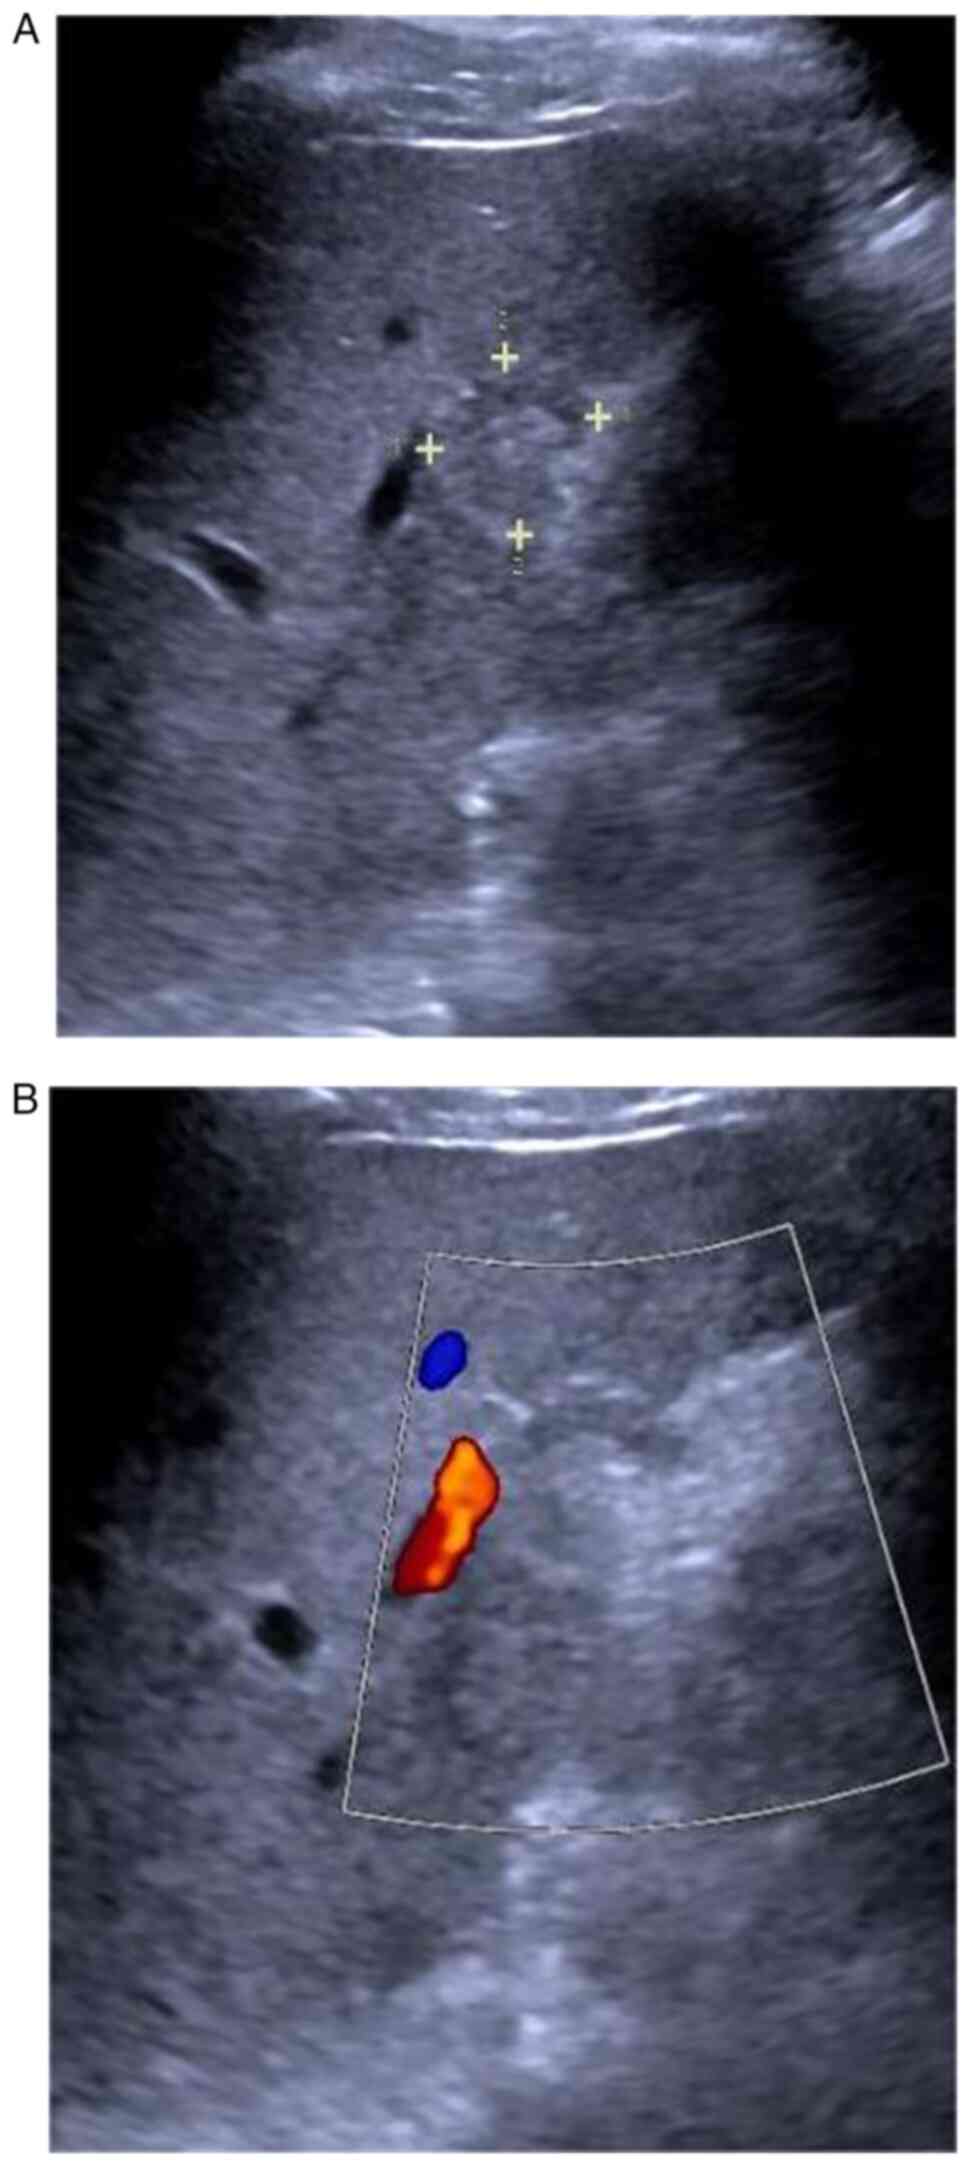

Characteristic contrast‑enhanced ultrasound findings of hepatic epithelioid haemangioendothelioma: A case report and literature review

Hepatic epithelioid hemangioendothelioma (HEHE) is a rare liver tumor, which is usually diagnosed by pathological examination, since the diagnostic imaging criteria remain to be defined. However, contrast‑enhanced ultrasound (CEUS) may reveal the characteristic features of HEHE to aid diagnosis. In the present study, two‑dimensional ultrasound examination of a 38‑year‑old male patient showed a mass in the right liver. CEUS showed an S5 segment hypoechoic nodule, and imaging features resulted in the diagnosis of HEHE. Surgery was shown to be an appropriate and successful treatment for HEHE. In conclusion, CEUS may be valuable for the diagnosis of HEHE, thereby avoiding the serious consequences of misdiagnosis.

Figure 1

Figure 2

Figure 3